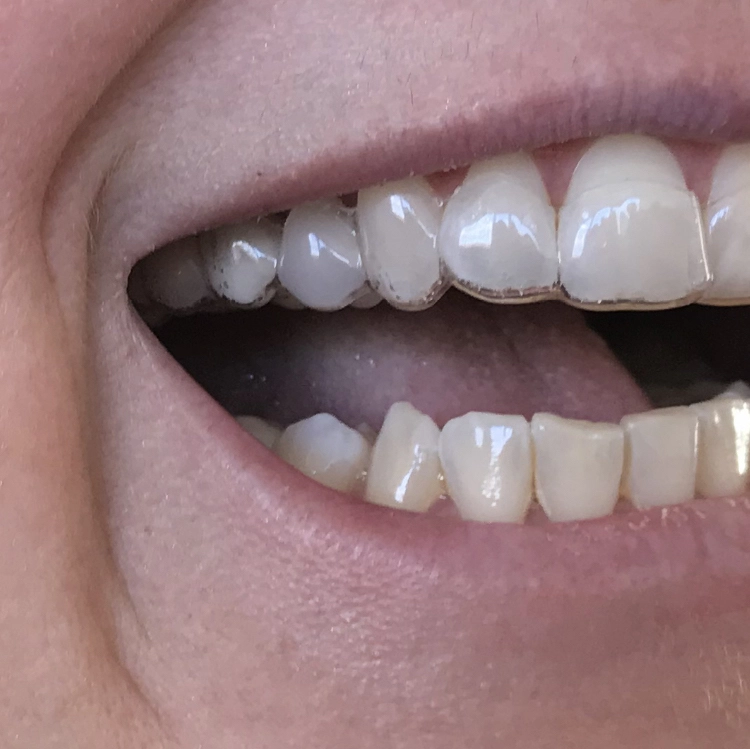

Die Implantate wurden provisorisch versorgt (Abb. 17). Kontrolle nach einer Woche mit Nahtentfernung (Abb. 18). Präparation und Abformung nach zwei Wochen.

Das alte Titanimplantat (20 Jahre in situ) bekam auch einen Zirkonaufbau (Abb. 19). Nach drei Wochen erfolgte die defi nitive Versorgung mit nicht-verblockten Zirkonkronen (Abb. 20).

Kontrollbild und Röntgenkontrolle ein Jahr und ein Monat nach Socket/Ridge Preservation (Abb. 21 und 22). Der komplette Umbau zu Eigenknochen ist noch nicht abgeschlossen. Die Papillenregeneration zwischen 13/14 und 14/15 ist jedoch deutlich erkennbar.